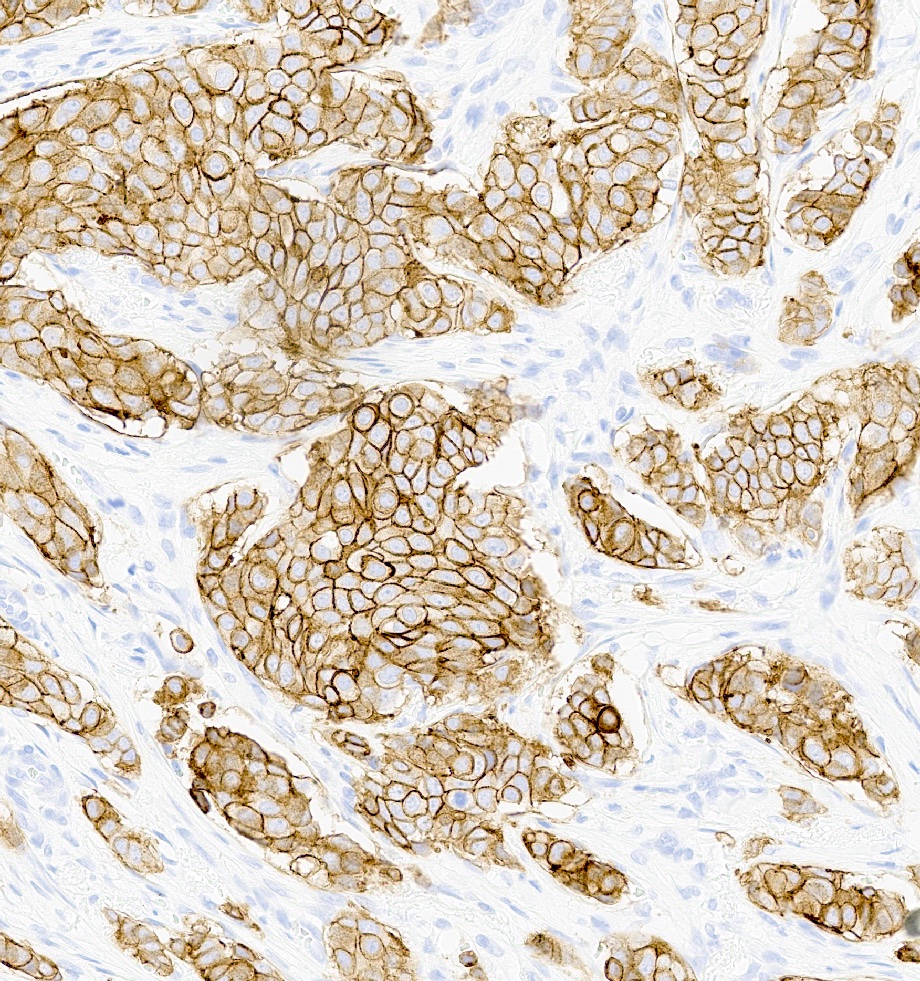

Positive stains

- High molecular weight basal cytokeratins: CK5/6, CK14, CK17 (Clin Cancer Res 2007;13:4429)

- EGFR (J Lab Physicians 2015;7:79)

- TRPS1 (positive in 86% of triple negative and metaplastic carcinomas)

- GATA3 (nonmetaplastic: 51%, metaplastic: 21%)

- HER2 enriched